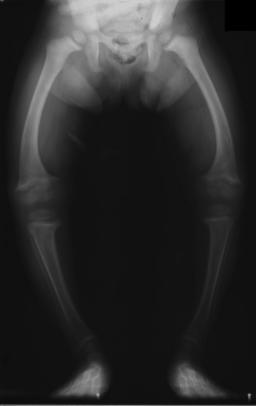

Rickets

Rickets is defective mineralization of osteoid that effects children.

Low vitamin D levels in children cause improper bone mineralization, which causes rickets.

Common features of rickets include:

- Frontal bossing

- Large forehead

Frontal bossing or having a larger forehead due to osteoid deposition on the skull is another common symptom of rickets in children.